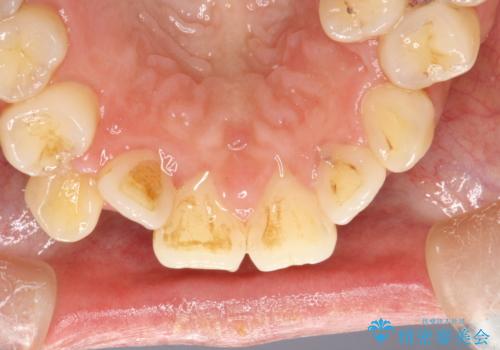

プラーク(細菌の塊)や歯石がたまると歯の表面はザラつきいてきます。そのザラつきは歯周病や虫歯菌の棲家となります。そのまま放置すると、歯肉が腫れてきたり、歯肉から出血したり、口臭が強くでたりします。とくに歯肉の境目は、歯磨きで汚れを除去することが難しく、プラーク(細菌の塊)や歯石が溜まりやすい場所です。

歯並が、がたついている場合はなおさら汚れが溜まりやすいです。矯正治療前や定期的にPMTCをすることで、矯正治療中の歯肉トラブルを防ぐことにつながります。